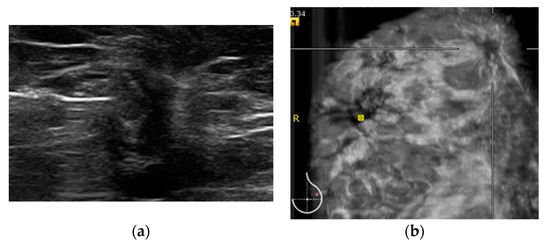

2.2. HHUS Examination

2.3. ABVS Execution